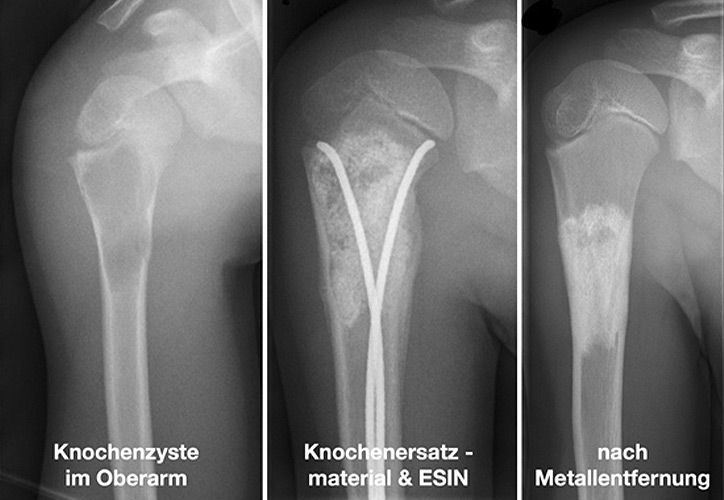

Knochenzysten

Knochenzysten sind die häufigsten gutartigen tumorähnlichen Knochenläsionen im Kindes- und Jugendalter und machen in großen Sammelstatistiken 13-19% dieser Läsionen aus. Es werden die juvenilen und aneurysmatischen Knochenzysten unterschieden. Der Altersgipfel für die meist zufällige Erstdiagnose liegt zwischen dem 9. und 13. Lebensjahr. Die Lokalisation der Knochenzyste verteilt sich nach Literaturangaben auf den Oberarm (ca 50%), den Oberschenkel (ca 30%), den Unterschenkel (ca 10%), aber sie können an allen Knochen vorkommen. Die genaue Pathogenese ist unklar, es werden jedoch lokale Wachstumsstörungen in der Entstehungsphase des Röhrenknochens diskutiert.

Um pathologische Frakturen zu verhindern, stehen mehrere Möglichkeiten zur Verfügung, z.B.:

• chirurgische Entfernung (a.G. der Größe meist nicht möglich)

• Stabilisierung und gleichzeitige Therapie durch ESIN (Nagelung)

• Auffüllung mit Knochenersatzmaterial oder körpereigenem Knochen

• Kombinationstherapie mit Knochenersatzmaterial und ESIN (Abbildung)